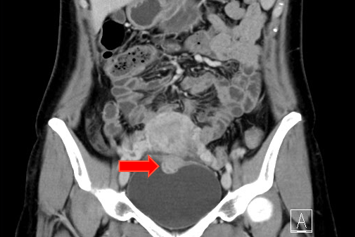

1.超声下可见一2.6cm结节。

2.妇科检查:外阴已婚型,阴道畅,宫颈暴露不佳,固定于耻骨联合后方,双侧附件未及异常;于阴道前穹窿可触及一质硬结节,大小约3cm。

3.盆腔MRI提示:膀胱占位结节,子宫内膜异位结节可能。

1.膀胱子宫内膜异位症